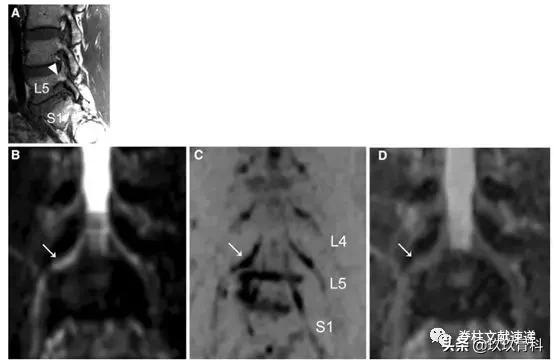

图注:66岁男性患者,L5-S1椎间孔狭窄,箭头显示L5椎间孔狭窄,神经周围脂肪信号消失。L4、L5和S1显示腰4、5和骶1神经根。D图是基于DWI冠状面计算的ADC图。箭头所示为被夹住的神经向上移位,并在孔内横移。

图注:47岁患者,L5/S1椎间盘突出。箭头显示L5椎间孔狭窄,神经周围脂肪信号消失。B图T2加权像,箭头显示孔内左侧椎间盘突出。E根据冠状面计算ADC图。箭头所示为神经根肿胀和凹陷。